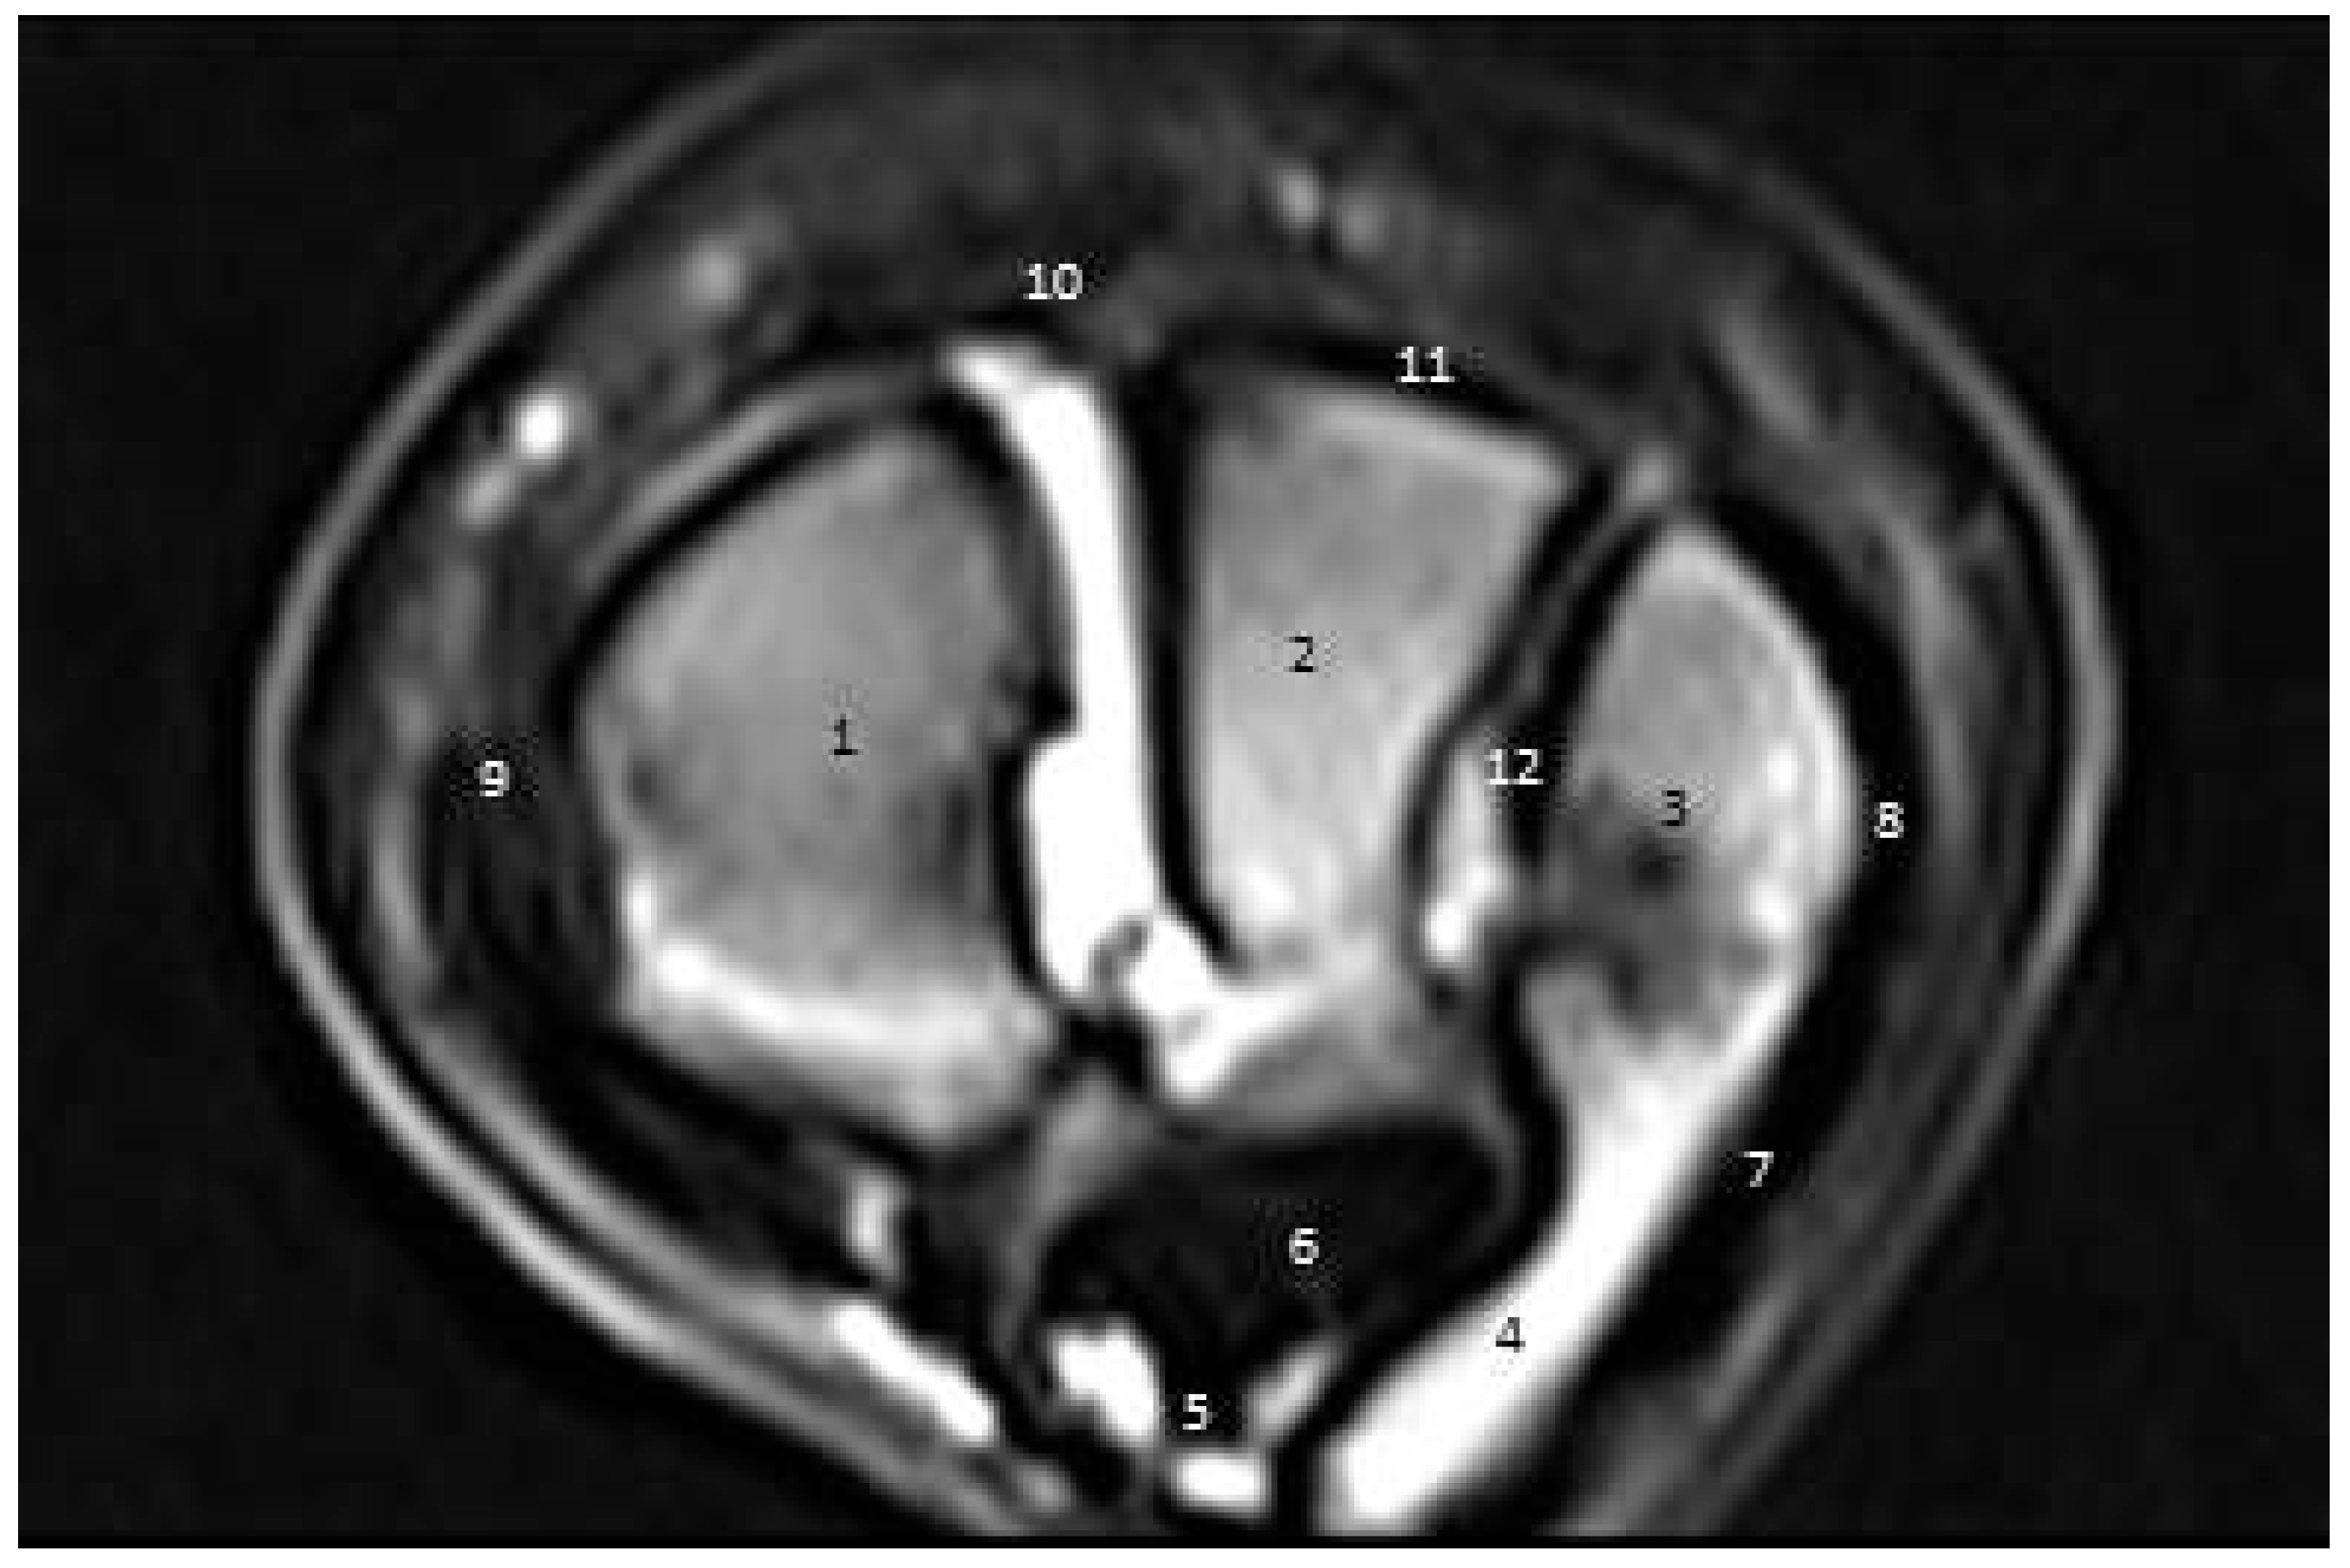

3.3.2. Second Zone